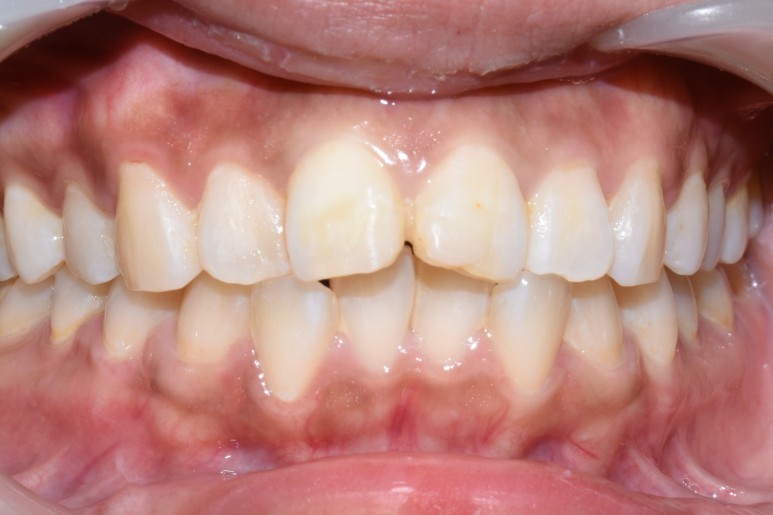

앞니가 깨져서 오셨을 때 처음 상태

넘어져서 앞니가 많이 깨져서 오셨는데

치료를 물론 받으셔야 하지만 회사에서 점심시간에 잠깐 나오신 거라

사회생활을 하기 위해 임시로 앞니를 떼워드린 후

치료를 진행하여 앞니 크라운이 완성되었습니다.

깨진 치아 크라운을 하시는 김에

삐뚤었던 앞니를 교정하는 효과와 치아 색을 더 밝게 하는 효과를 넣어드려서

2개만 치료했지만

나머지 치아들도 더 전반적으로 깔끔해 보이는 효과가 생겼습니다.